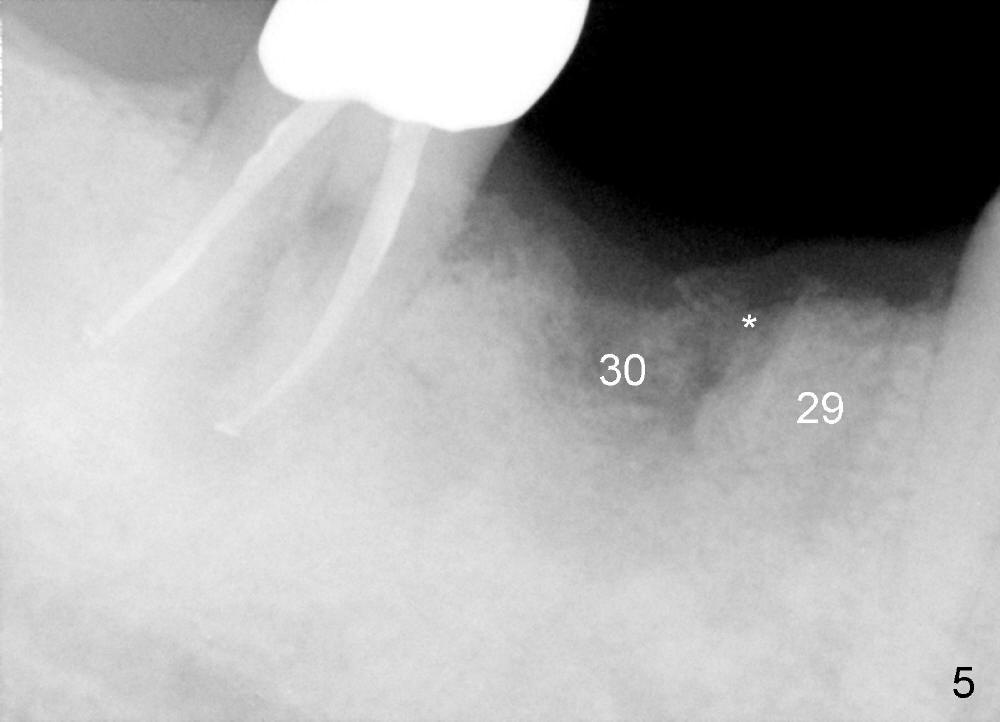

Three months later, the B-L width at the site of #29 is significantly reduced (Fig.4). Upon X-ray exam, there is decreased bone density between these two sockets (Fig.5 *). Socket preservation seems not to live its expectation. The obvious advantage is formation of callus-like bone in the molar socket (Fig.6 *, between the buccal (B) and lingual (L) plates). The significant decrease in the buccolingual width at the site of #29 is associated with buccal plate crack during implantation (Fig.7 *). At the site of #30, the lingual plate is so low that there is implant thread exposure (Fig.8 <). Mixture of autogenous bone (harvested from drilling with Bicon reamers) and synthetic bone (Osteogen) is placed mainly buccal to the implant #29 and lingual to #30 (Fig.9), followed by collagen membrane. Bone density between these two implant increases due to the bone grafting (Fig.10 *, as compared to Fig.5). In fact, the implant at the site of #29 is found loose 1 month postop.